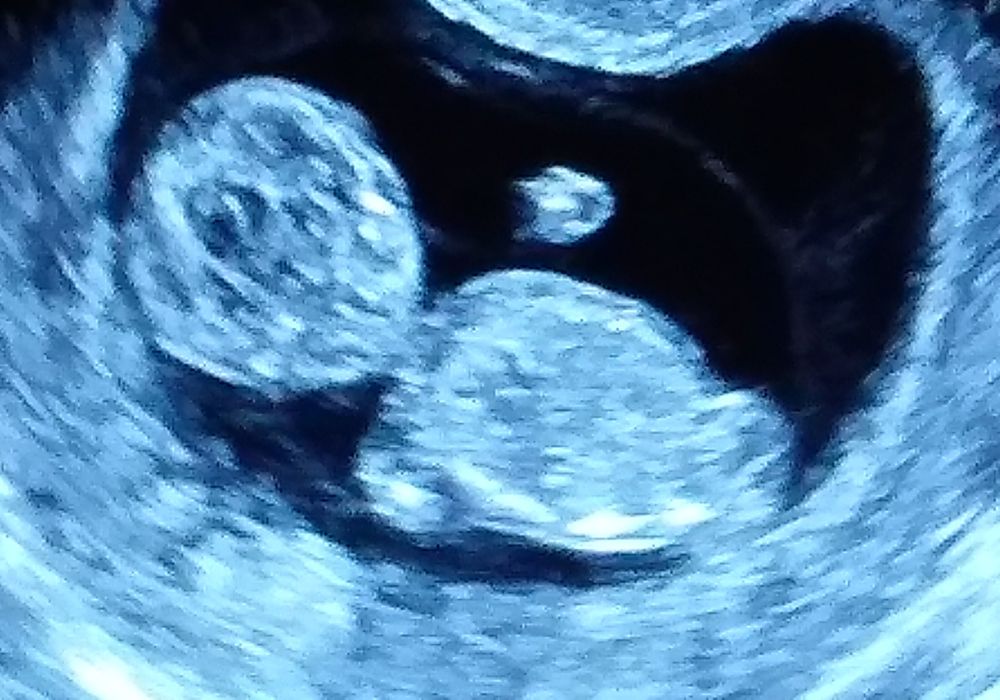

Ктр 54. Нос 1.8. Твп 1.3. Бедро 4.7. ЧСС 156 ♥️

Не распечатали, но разрешили сфоткать 😍

Пол у нас не предполагают, поэтому не паримся и ждём второго скрининга)очень интересно конечно, кто в домике, а по фото непонятно, лежит на боку и ничего не видно, только ножки согнутые👣